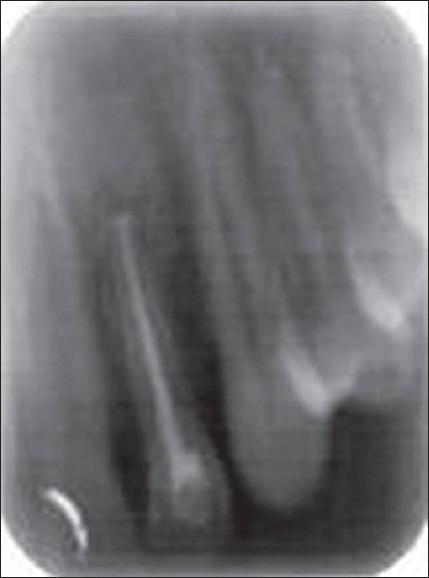

Calcium phosphate ceramics like hydroxyapatite and beta -tricalcium phosphate (beta -TCP) possess mineral composition that closely resembles that of the bone. They can be good bone substitutes due to their excellent biocompatibility. Biphasic calcium phosphate is a bone substitute which is a mixture of hydroxyapatite and beta -tricalcium phosphate in fixed ratios. Studies have demonstrated the osteoconductive potential of this composition. This paper highlights the clinical use of biphasic calcium phosphate as a bone substitute in periapical surgery.

磷酸钙陶瓷,如羟基磷灰石和β-磷酸三钙(β-TCP),具有与骨骼极为相似的矿物质组成。由于其出色的生物相容性,它们可以成为良好的骨替代物。双相磷酸钙是一种骨替代物,它是按固定比例混合的羟基磷灰石和β-磷酸三钙。研究已经证明了这种组合物的骨传导潜力。本文重点介绍了双相磷酸钙作为骨替代物在根尖手术中的临床应用。